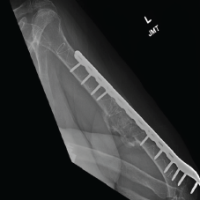

After detailed counseling regarding the nature of the lesion and treatment options, the patient consented to surgical intervention. A surgical approach was planned, and an open excisional biopsy was performed using a posterior reverse L-shaped incision (Burks-Schaffer approach) [7]. On posterior capsule opening, a 2.5 cm × 2.5 cm encapsulated mass was identified behind the PCL and was excised en bloc. The mass contained multiple white loose bodies, each approximately 5 mm in diameter (Fig. 3). Both the excised loose bodies and synovial tissue were sent for histopathological analysis. Histopathological examination identified nodules of hyaline cartilage with clustered chondrocytes, encased by synovial tissue of varying thickness, thereby confirming the diagnosis of SC (Fig. 4).

Post-operative rehabilitation included weight bearing as tolerated, along with knee range-of-motion exercises and isometric quadriceps and hamstrings strengthening. The patient was followed up at 1, 3, and 6 months postoperatively. At the final 1½ year follow-up, the patient demonstrated an active knee flexion-extension range of 0°–130° without discomfort with full weight-bearing gait without support.